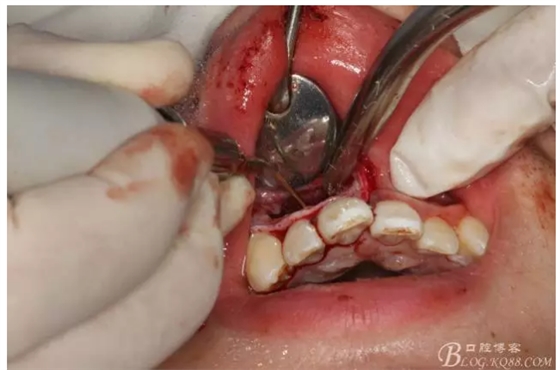

圖9.去除根尖3mm牙膠。

圖10.超聲骨刀去除的牙膠

圖11.MTA倒充填預備好的根尖3mm。